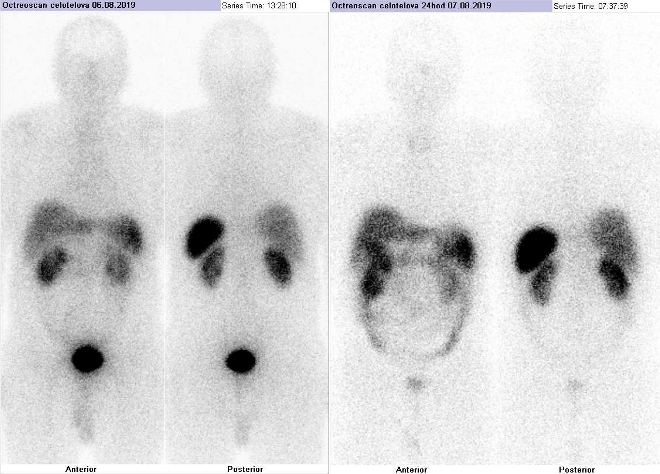

Pomocí dvoudetektorové hybridní tomografické kamery Symbia T2 (SPECT/CT) firmy Siemens opatřené kolimátory pro střední energie jsme provedli celotělovou scintigrafii a také cílenou tomografickou scintigrafii (SPECT) a CT a fúzi obrazů SPECT/CT břicha a pánve za 4 hod. a 24 hod. (obr. 1-3) po i.v. podání 190 MBq analogu somatostatinu značeného

111In (přípravek OctreoScan firmy Mallinckrodt Medical).

/ Obr.č.1: Celotělová scintigrafie v přední a zadní projekci. Vyšetření 4 hod. (vlevo) a 24 hod. (vpravo) po aplikaci radioindikátoru.

Popis: patologicky zvýšená depozice radiofarmaka pouze v malé části rozsáhlého tumoru při ložiskově zvýšené hustotě somatostatinových receptorů zřejmě v duodenu.

U 65letého muže s rozsáhlým neuroendokrinním tumorem žaludku zasahujícím do duodena a s postižením lymfatických uzlin jsme pomocí vyšetření Octreoscanem prokázali

ložiskově zvýšenou hustotu somatostatinových receptorů pouze v malé části rozsáhlého tumoru zřejmě v duodenu. Většina tumoru patrného na ldCT včetně postižených lymfatických uzlin radiofarmakum neakumuluje. Nejspíše je to dáno tím, že tumor je dediferencován.